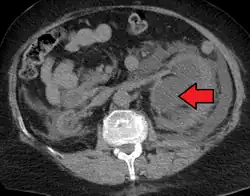

Massive hydronephrosis as marked by the arrow